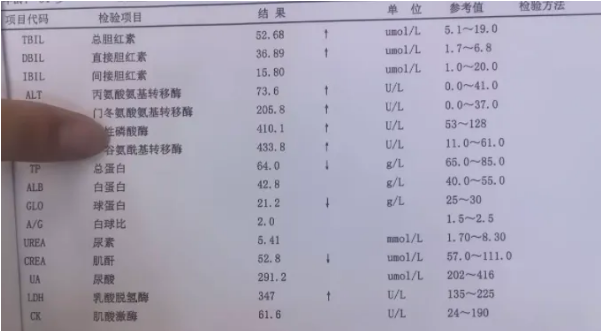

患者入院时,腹痛、呕吐症状已持续数小时。初步血液检查提示存在明显的梗阻性黄疸及肝损伤迹象:总胆红素、直接胆红素等指标显著升高。这强烈提示胆汁排泄通路可能受阻。